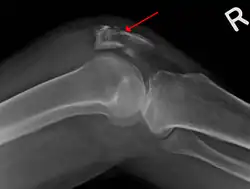

| A fracture of the patella seen on a lateral view | |

The patella can break in various ways depending on the way it is injured, and into two or more pieces.[1] Types include transverse, the most common, with one fracture line;[5] marginal; osteochondral; and the rare vertical type, or stellate, where a direct compression force gives rise to a comminuted pattern.[5][7] Patella fractures can be further classified as displaced, where the broken ends of bone do not line up correctly and separate by more than 2mm, or undisplaced and stable where pieces of bone remain in contact with each other.[1][7] If fragments of patella bone stick out from the skin it is known as an open patella fracture, and closed if the overlying skin is intact.[1]

-

Transverse fracture of patella -

Comminuted fracture of patella -

Osteochondral fracture of patella -

Vertical patella fracture